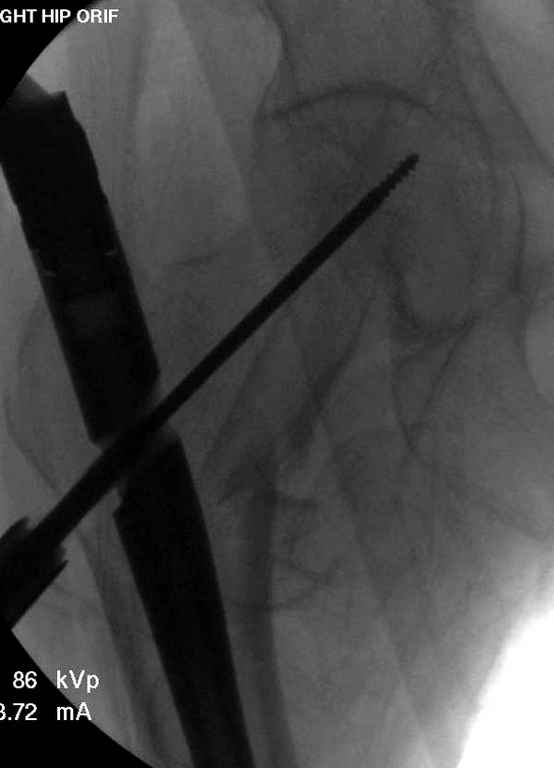

Вашему вниманию представляется похожий случай, пациентке 70, осложнился в течение одного месяца после операции. Ревизия с заменой сустава, кабельная фиксация на трохантер. При установке в дистальном диафизе обнаружен тонкий кортикальный слой и сделана профилактика от возможного перелома аллографтом.